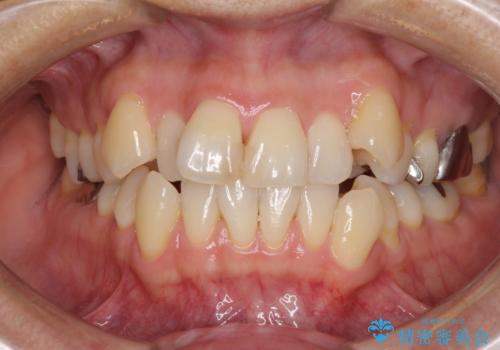

八重歯で口元が膨れている ワイヤー装置での抜歯矯正